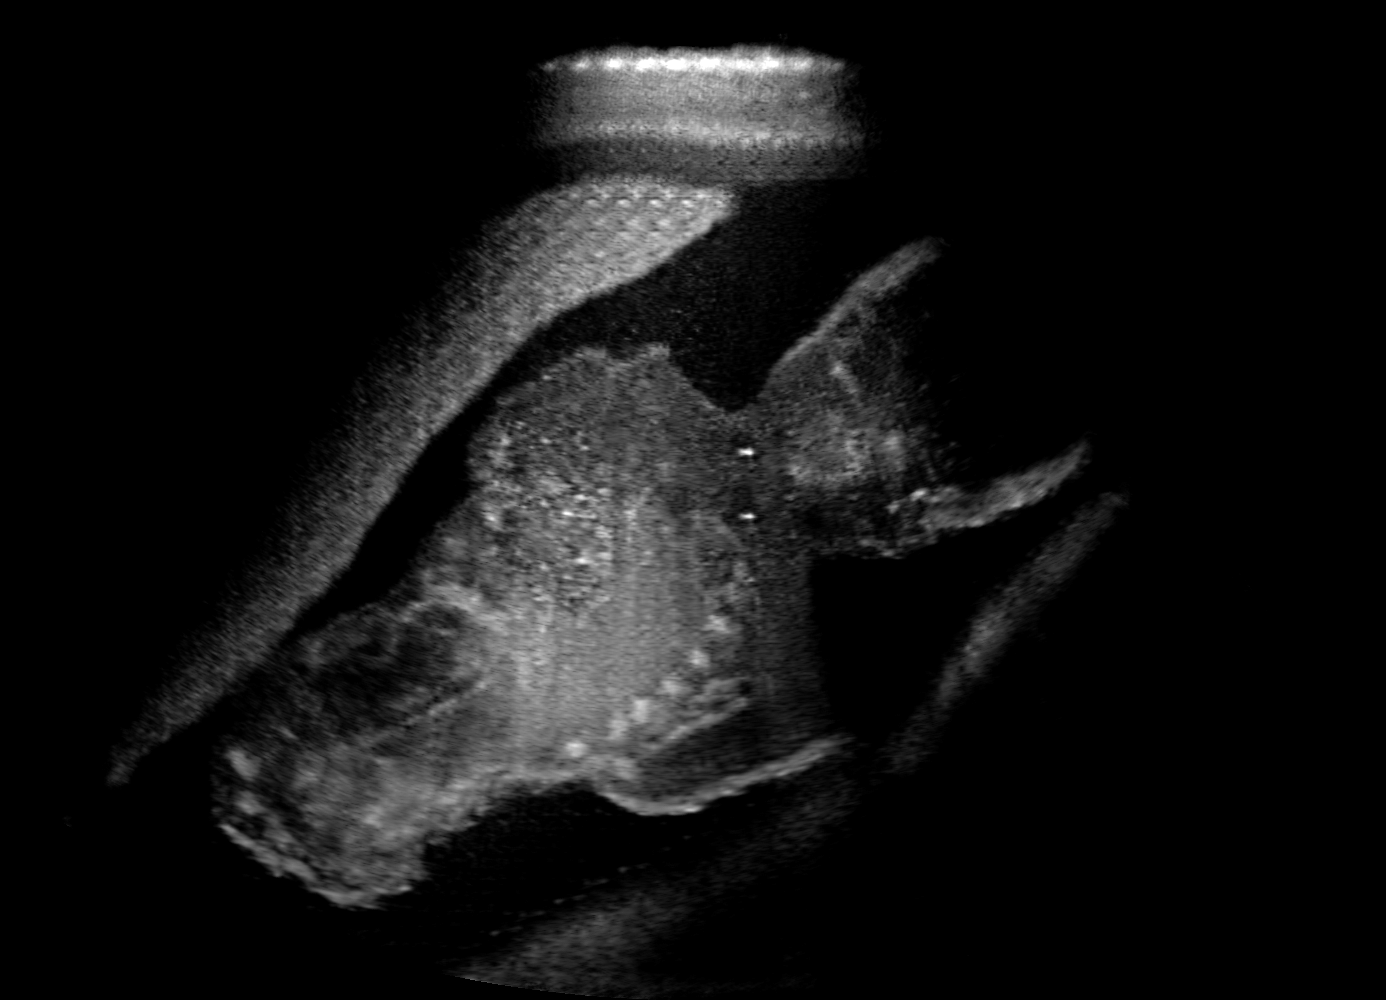

Qualitative evaluation.

Fig. 2 depicts the qualitative results for all the models mentioned above, with arrows pointing at structures relevant to discussion points below. The visual results of the ablated variants of SA2H show substantial quality degradation compared to the full SA2H model, demonstrating the importance of each proposed architectural contribution. Given only segmentation map in the network input, SA2H-att fails to generate acoustic shadows, e.g. those cast by the ribs. Detailed structures such as the cervical vertebrae are blurred out in the SA2H-concat results, which also contain hallucinated structures mainly due to insufficient preservation of input information along the encoding-decoding path. With SA2H-conv, checkerboard artefacts are observed due to the lack of proposed additional stride-1 convolutional layers. SA2H-noise without any explicit noise input is seen to be sub-optimal at generating textural details. The baseline method NSA2H fails to preserve anatomical structures and acoustic shadows in all cases, while the simulated textures also show significant artefacts such as checkerboard patterns. Realism of different simulation aspects may become relevant given different clinical applications and scenarios. For instance, improved structural preservation, e.g. with the hyperechoic bony structures such as the skull and the ribs, of the final model over its ablated variants and NSA2H may prove relevant in fetal head measurements, while the textural improvements facilitating screening fetal organ maturity, e.g. lungs. Compared to the silver-standard model LSA2H with a low-quality rendered image as additional input, SA2H is seen to be on par in structural preservation. Note that shadowing on homogenous regions (e.g. the rib shadowing on the homogenous lung region on the 4th column of Fig. 2) with our proposed method SA2H is represented more faithfully compared to LSA2H, whereas shadows on structurally complex regions (e.g. the skull shadowing around the heart and surrounding tissues on the 3rd column of Fig. 2) are suboptimal with our SA2H. Therefore, one may have to evaluate our method given particular simulation tasks, e.g. its clinical validity for fetal heart exams. However, even with low quality rendered images, LSA2H leads to artificial enhancements of intensities, lack of acoustic shadows, and low-quality textures especially near the probe, for which SA2H yields satisfactory results as illustrated in Fig. 2.

(a) Target

(b) SA2H

(c) SA2H-att

(d) SA2H-concat

(e) SA2H-conv

(f) SA2H-noise

(g) NSA2H

(h) LSA2H